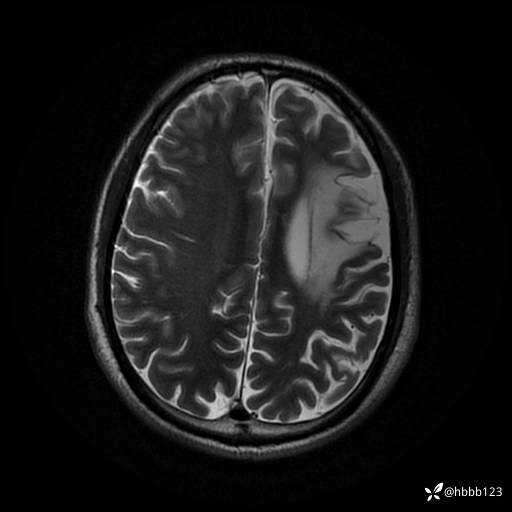

患者男,43岁。

简要病史:癫痫患者复诊,昨日发作5-6次,建议住院进一步治疗。

入院完善脑癫痫组合序列:

T2: